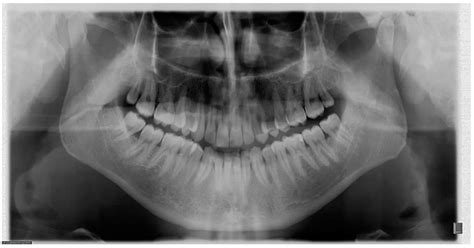

Radiografiile Dentare în Sarcină

Radiografiile dentare pot fi efectuate în timpul sarcinii doar atunci când sunt absolut necesare (ex. tratament de canal, traumatisme). Cantitatea de radiație este minimă (o radiografie dentară periapicală emite 0,1 mrad), iar riscul pentru făt este extrem de scăzut (de mii de ori mai mic decât riscul de malignitate asociat cu 1 rad de expunere). Se recomandă utilizarea unui șorț protector de plumb și a metodelor moderne de radiografie cu film rapid pentru a limita expunerea.